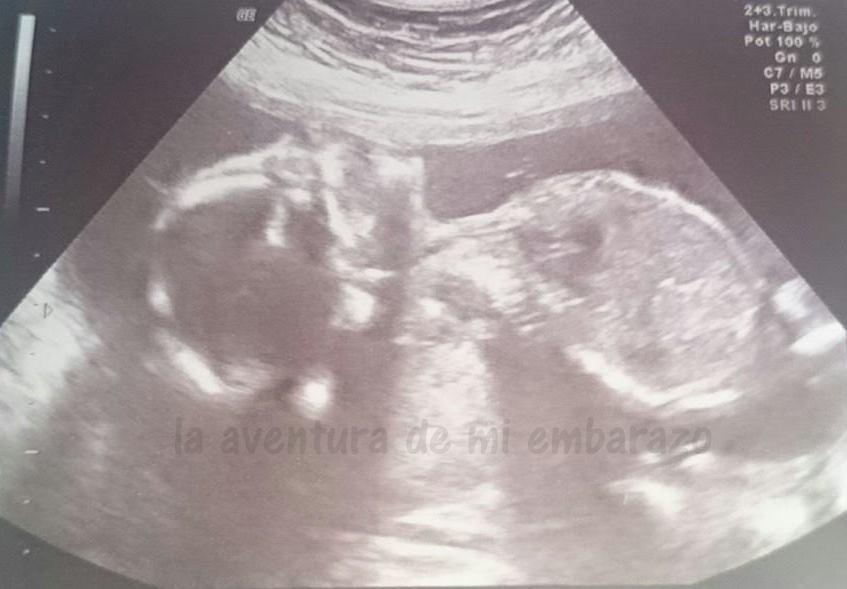

Por tamaño corresponde aproximadamente al tiempo de gestación, todas las medidas unos días por encima pero en general acorde a 21 semanas -la ecografía fue de 20+4-, aunque admito el margen de error porque a la residente le costaba afinar con el transductor. De hecho, no consiguió cogerlo bien para una buena foto, pero bueno, menos es nada.

photo eco-20semanas_zpsbfvpnja9.jpg

Y su entorno perfecto también, el líquido amniótico en cantidad adecuada, placenta en posterior, nada que objetar, afortunadamente. Disipados mis temores de que mis escapes sean líquido amniótico, es algo que me ha dejado muy tranquila.